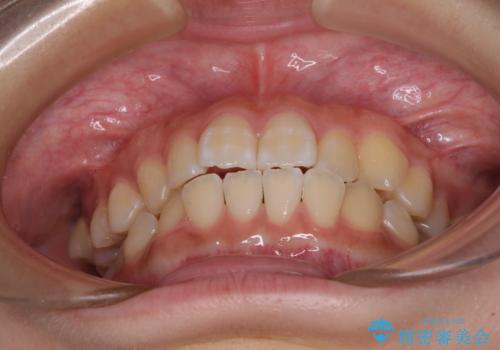

- 前歯のデコボコと磨きにくい奥歯を気にして来院された患者様です。

左右ともに上顎第二大臼歯が外側に転位しており、大変磨きにくくなっているため、補助装置により内側に引き込むことで改善することとしました。

外側を向いていた奥歯は比較的早い時期に歯列に収まり、咬み合わせも磨きやすさも改善することができました。

歯列は元々悪くなかったので、1年ほどで治療を終えることができました。